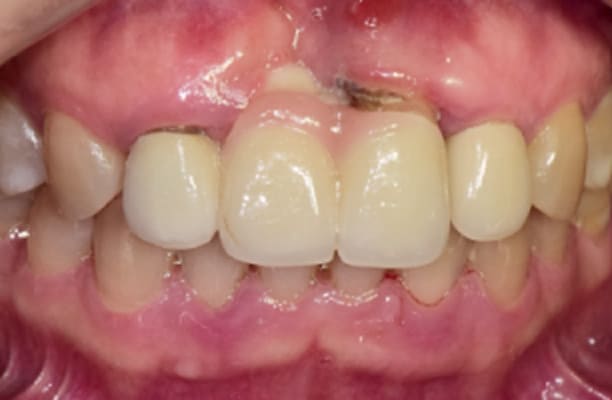

临床案例

-

术前 -

术后